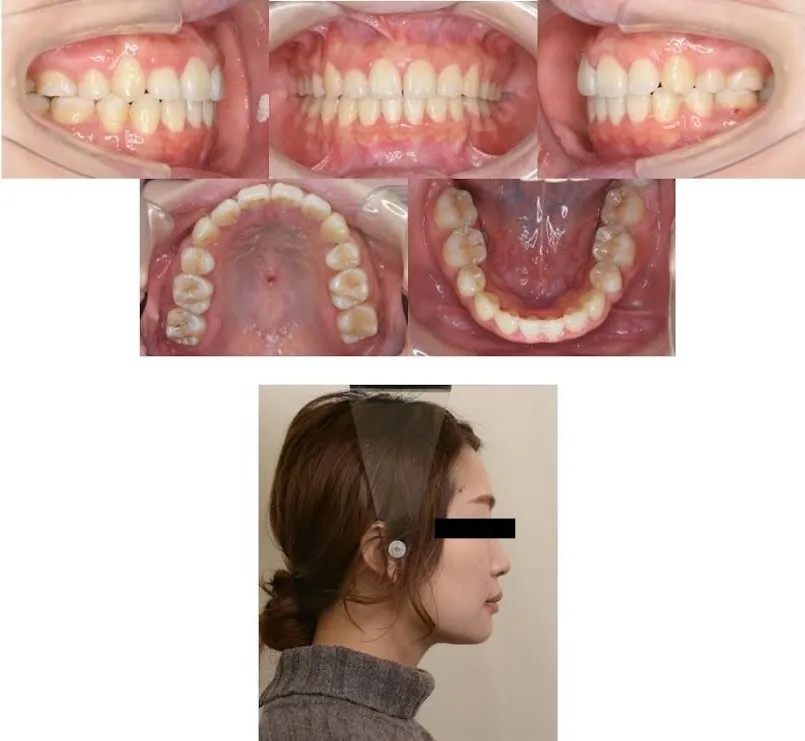

施術後

治療後